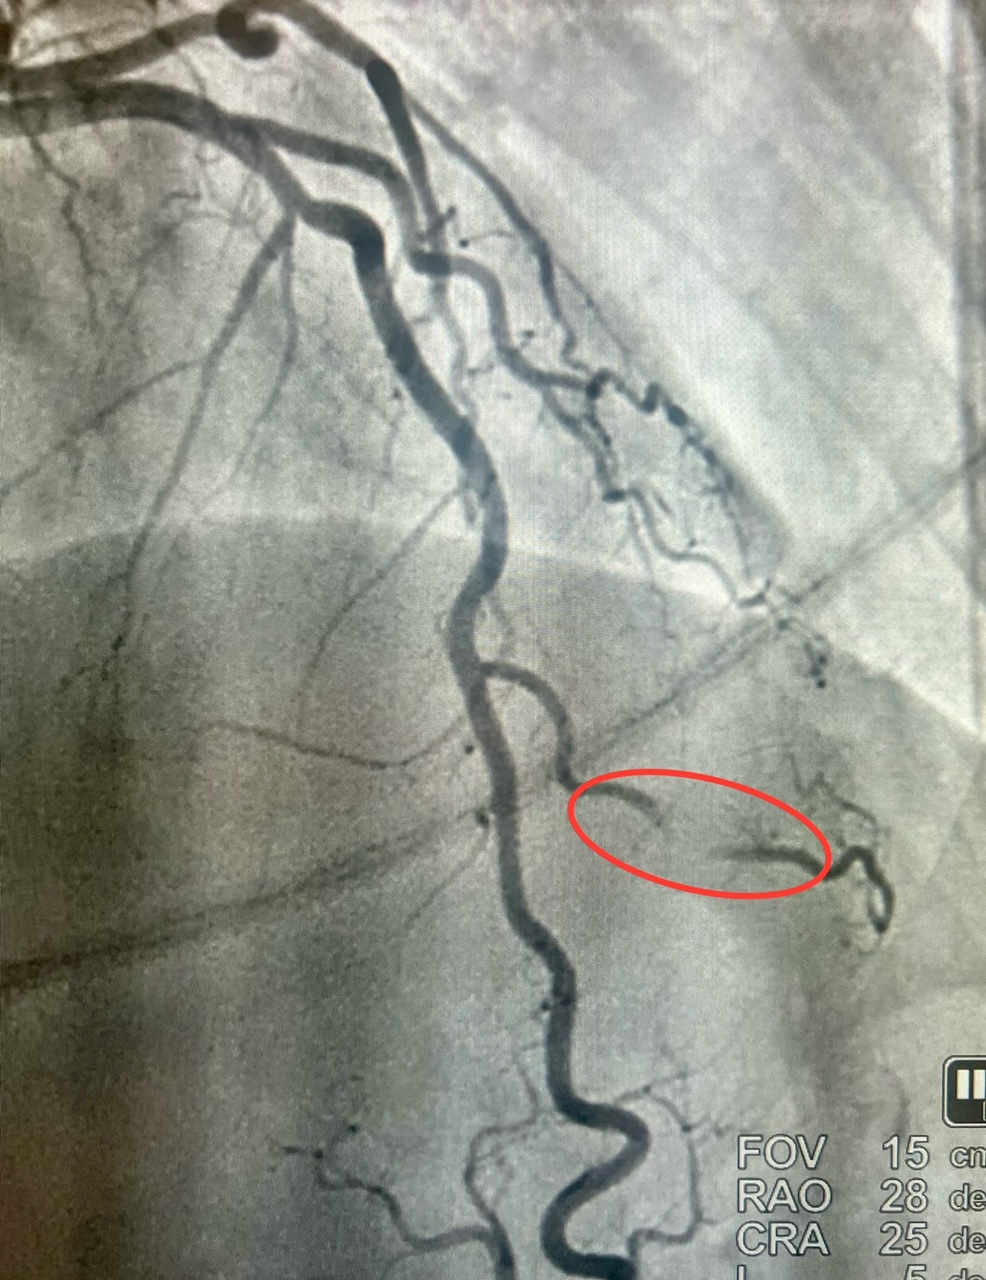

We present a 54-year-old woman with a medical history of opioid addiction, anxiety disorder, and current cigarette smoker who presented to the hospital via Emergency Medical Service after an episode of syncope at home. (Figures 1 and 2). The patient continued to have recurrent episodes of ventricular tachycardia along with elevated troponins, with an echocardiogram that showed reduced LV ejection fraction with slightly more pronounced hypokinesis of the septal and apical walls; thus, the decision was made to rule out ischemia as a possible cause. She subsequently underwent coronary angiography via the right radial approach, which revealed a right-dominant system, and normal coronary arteries, with the exception of the second diagonal branch of the LAD, which had severe systolic compression, resulting in obliteration of the artery with each cardiac cycle. Angiographically, when a vessel completely obliterates during cardiac catheterization, it is referred to as a “milking” phenomenon (Video).